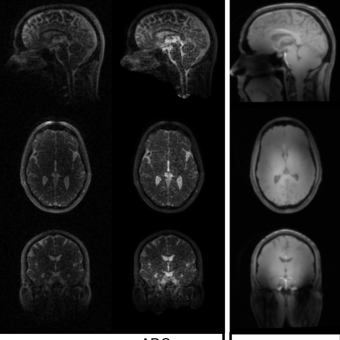

Image Courtesy: J.M. Kommen, DKFZ Heidelberg, Germany

23Na MRI data from 30-channel array data reconstructed using ADC (1st column) and B1– corrected ADC (2nd column). Anatomical details become clearly visivible. The 1H data displays good field homogeneity (3rd column).